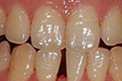

3D超薄贴面

快速解决以下牙齿问题 龅牙、虎牙、老鼠牙、氟斑牙、牙齿拥挤、四环素牙、畸形牙、牙齿稀疏

根据求美者牙齿的高低厚薄进行3D精细化量齿定制,并预先设计出贴面效果,创3D工艺,量齿订制,大量应用黄金比例,将各种可能效果进行比 较,设计出适合的贴面,是目前高品质的瓷贴面术。

技术特点:技术特点:① 不磨牙 不脱落; ② 量齿定制 个性化; ③ 贴片超薄 无色差; ④ 美观耐用 不伤牙神经;